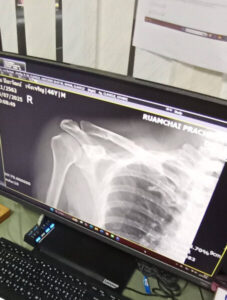

เมื่อเวลา 11.00 น.วันที่ 4 มี.ค.69 ผู้สื่อข่าวได้เดินทางไปที่ ต.คลองด่าน อ.บางบ่อ จ.สมุทรปราการ พบกับนายปิยวัฒน์ เจ้งเจริญ อายุ 46 ปี ที่อยู่ตามบัตรประชาชนเลขที่ 199/3 หมู่ที่ 13 ต.คลองด่าน อ.บางบ่อ จ.สมุทรปราการ หอบหลักฐานเป็นใบแจ้งความ ใบรับรองแพทย์และคลิปจากกล้องวงจรปิดขณะเกิดเหตุ มาให้ผู้สื่อข่าวดู โชว์ร่องรอยอาการบาดเจ็บที่ไหปลาร้า พร้อมเล่าเรื่องราวที่เกิดขึ้น

นายปิยวัฒน์ เจ้งเจริญ ผู้เสียหาย กล่าวว่า เหตุการณ์นี้เกิดขึ้นเมื่อวันที 11 ก.ค.69 เวลาประมาณ 02.00 น.ขณะที่ตน ซ้อนท้ายรถ จยย.น้องชาย โดยมีหลานวัย 2 ปี นั่งมาด้วย จะพากันไปกินข้าวมันไก่ ขับขี่โดยใช้เส้นทางปกติ เมื่อเลี้ยวซ้ายออกมาจากซอยโรจนกุล เห็นเงามืดอยู่บนถนน เข้าใจว่าเป็นเงาของเสาไฟฟ้า จึงขับขี่เพื่อผ่านไป จู่ ๆ รถเสียหลักล้ม ทุกคนลงไปนอนกองกับพื้นถนน น้องชายที่เป็นคนขับขี่กับหลานวัย 2 ขวบ บาดเจ็บเล็กน้อย ส่วน ตนรู้สึกเจ็บปวดที่ไหล่ด้านขวา หลังเกิดเหตุมีพนักงานที่ทำงานอยู่ในบ่อขุดเจาะทำทางลอดสายไฟฟ้าใต้ดิน ขึ้นมาดู ช่วยยกรถ จยย.แล้วก็เดินกลับไป ส่วนสาเหตุที่ทำให้รถ จยย.ล้ม เพราะคนงานเอาท่อยางสีดำขนาดเส้นผ่าศูนย์กลางประมาณ 12 นิ้ว มาวางไว้อยู่บนถนนโดยไม่มีสัญญาณไฟ หรือ ป้ายเตือนใด ๆ ทำให้คนใช้รถใช้ถนนมองไม่เห็น ขับพุ่งชนได้รับบาดเจ็บ หลังจากไปโรงพยาบาล พบว่าไหปลาร้าหัก ตนต้องจ่ายค่ารักษาพยาบาลเอง เป็นเงินกว่า 19,000 บาท (หนึ่งหมื่นเก้าพันบาท) ซึ่งได้พูดคุยกับตัวแทนของบริษัทรับเหมาก่อสร้าง ที่ สภ.คลองด่าน ในคืนนั้น แจ้งว่าจะส่งเรื่องไปที่บริษัทเพื่อให้รับผิดชอบ แต่ผ่านมา 6 เดือนยังไร้การดูแลเยียวยาและไม่เคยมาเยียม